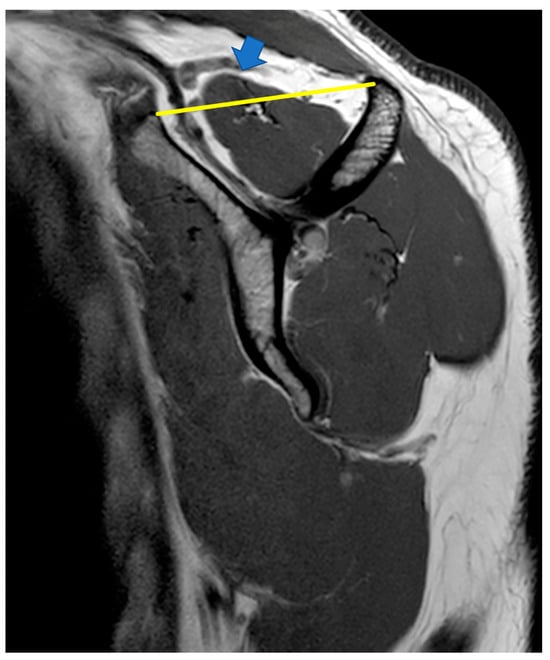

- Positive tangent sign

indicates level of supraspinatus tendon retraction.

indicates supraspinatus extending above the tangent.